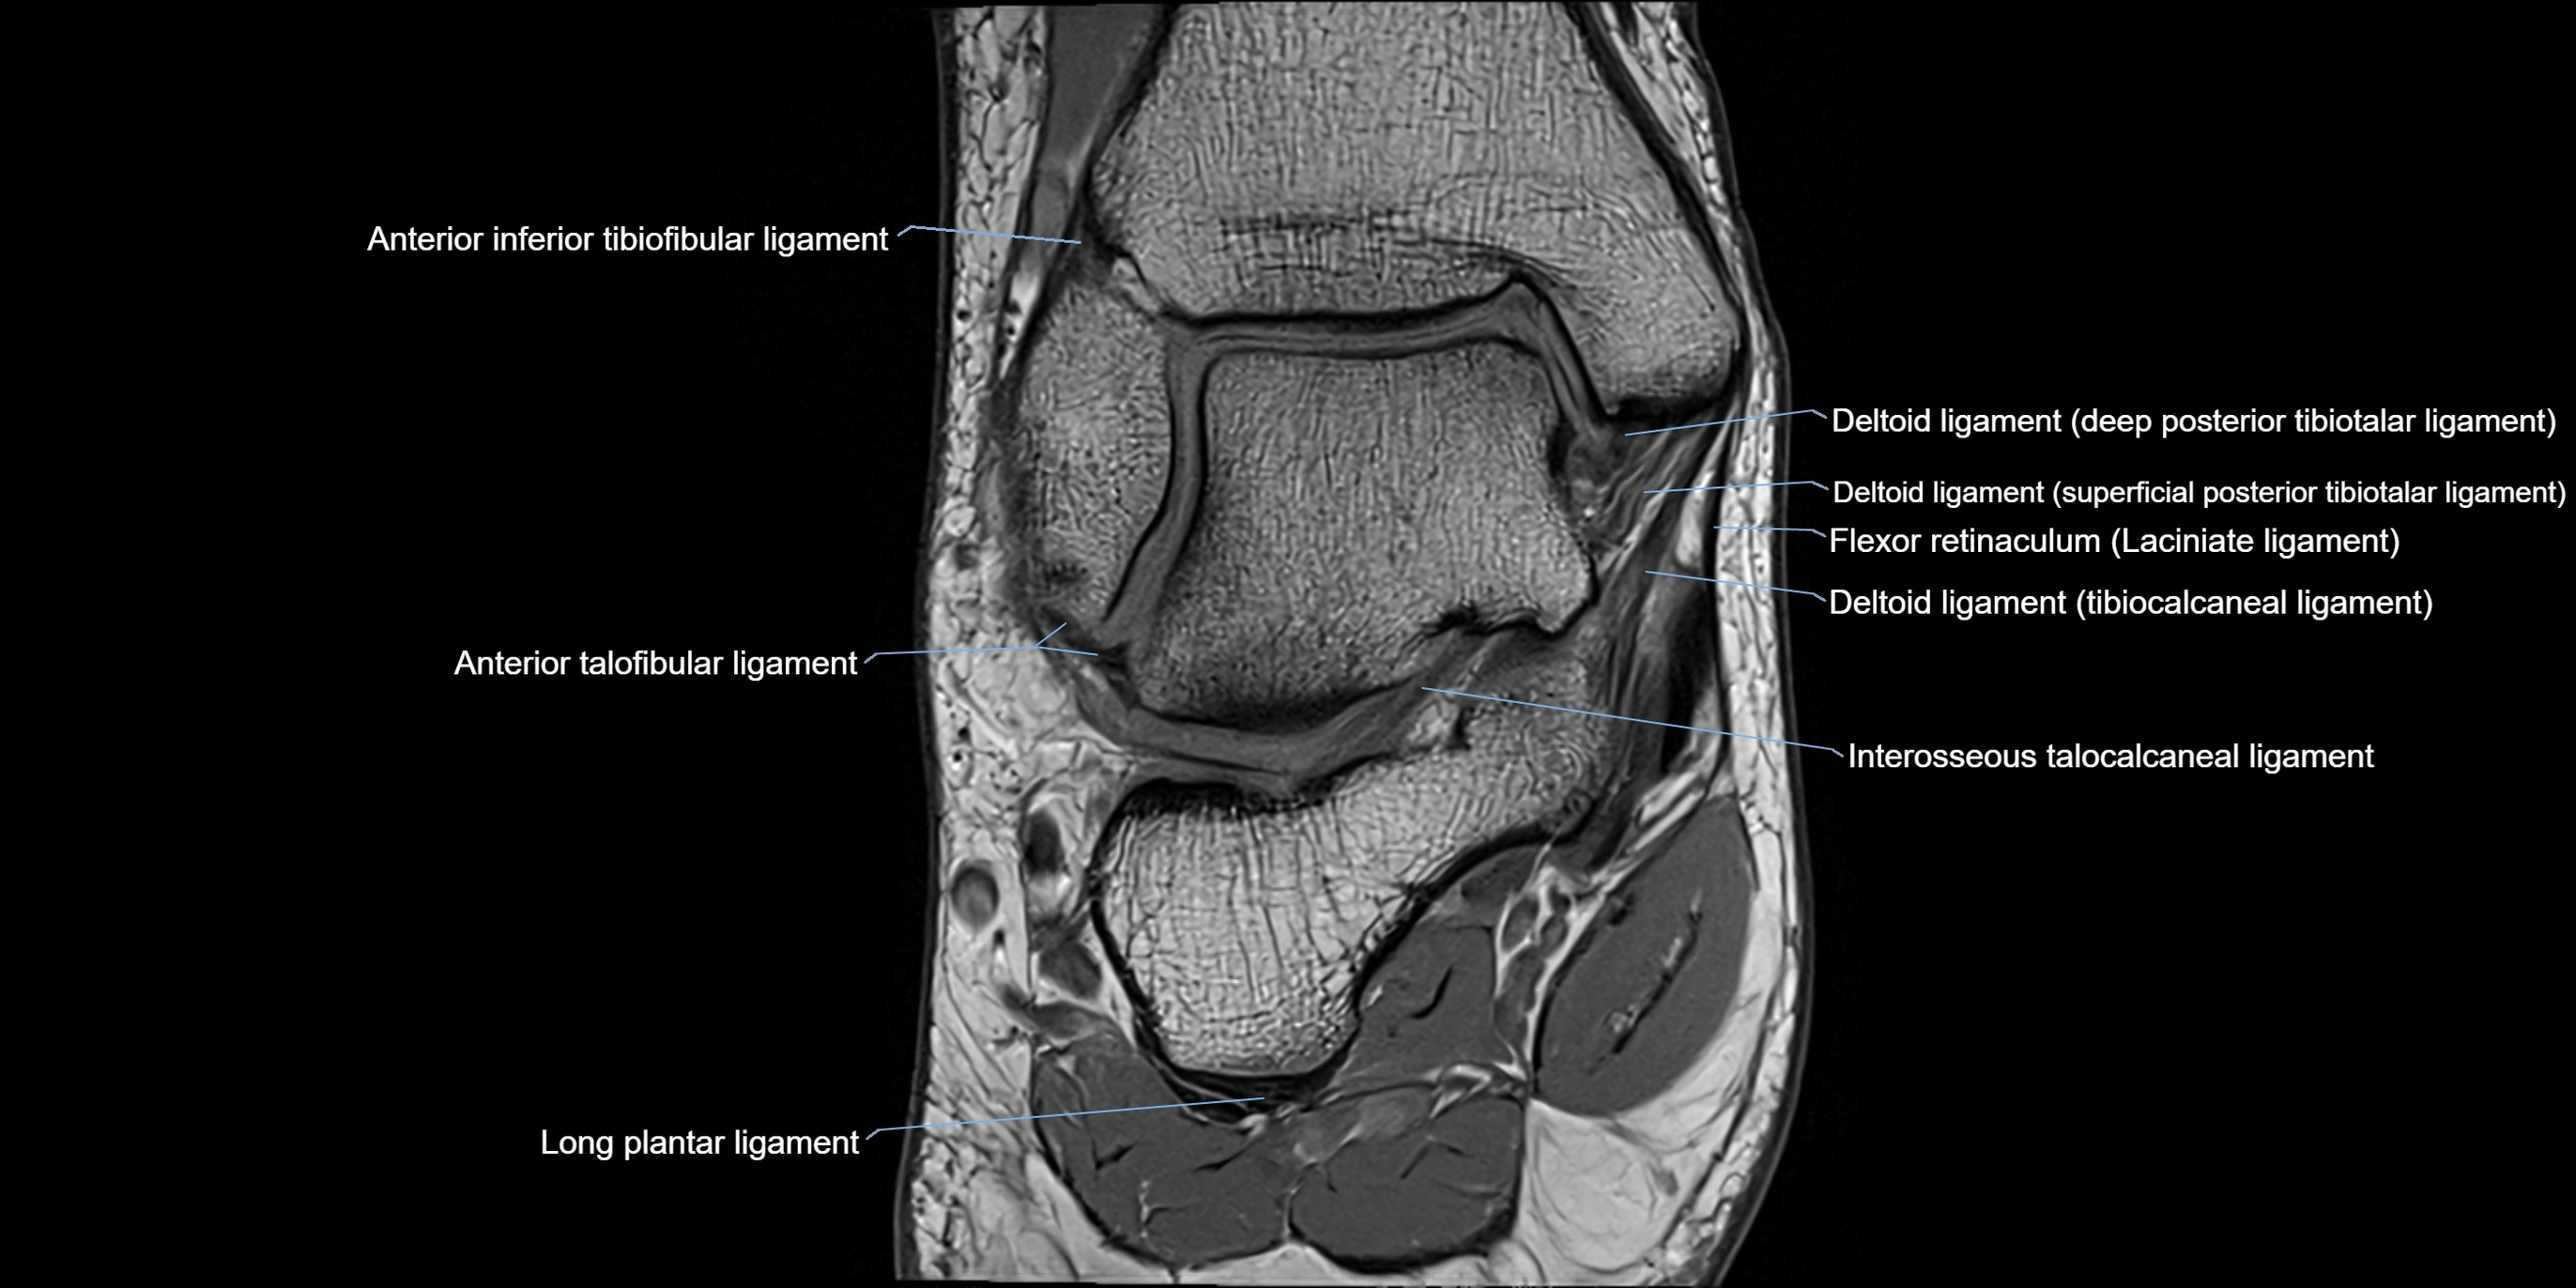

MRI image

image